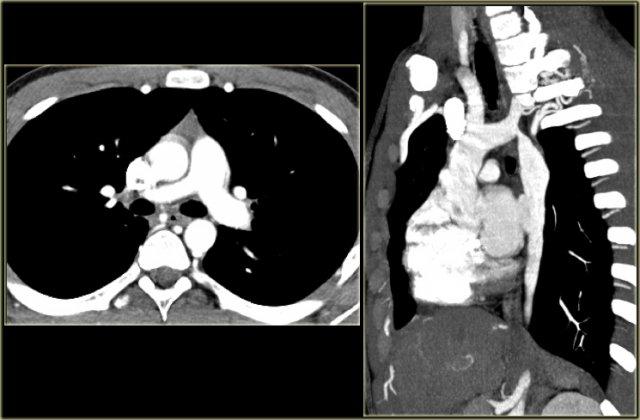

On the left the reconstructions demonstrating a double aortic arch.

There are branches coming off the right arch and branches coming off the left arch.

The right arch is typically larger and higher than the left.

There is a complete ring that encircles the esophagus and the trachea and usually there is stridor or dysphagia.

Two brachiocephalic arteries arise on each side separately (four vessel sign).

On the left axial images and posterior view of volume rendered reconstruction.

The findings are:

- four vessel sign

- double arch

- right arch higher and larger

- esophagus and trachea are completely encircled

The narrowing of the trachea is seen on the axial images, but better appreciated on the MPR and Volume Rendered image.